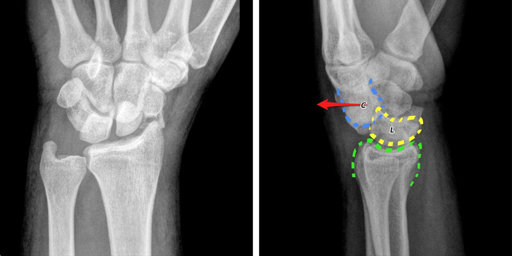

Nhiều người đã biết đến phương pháp chụp X - quang khi có nghi ngờ chấn thương liên quan đến xương, khớp. Vậy chụp X - quang cổ tay được thực hiện như thế nào để mang lại hiệu quả trong điều trị và cải thiện sức khỏe? Cùng tìm hiểu các thông tin đó qua bài viết dưới đây.